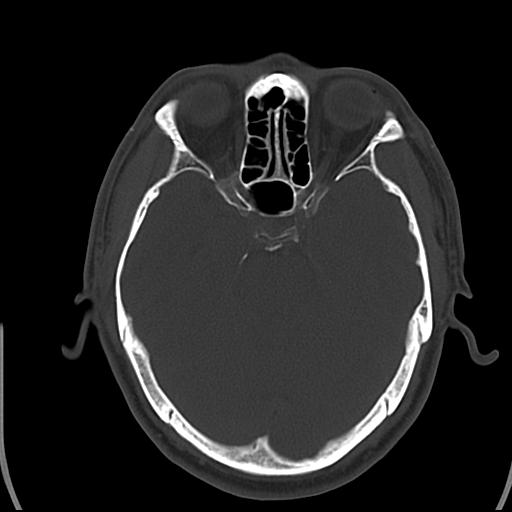

头皮下高密度结节影???临床上在老年男性比较常见。大家看看是什么?成因是? 本例患者,男性,51岁。外伤来诊。无染发史及发根植入史。

皮下钙化点

没见过,可能为毛囊钙化。

考虑钙化。